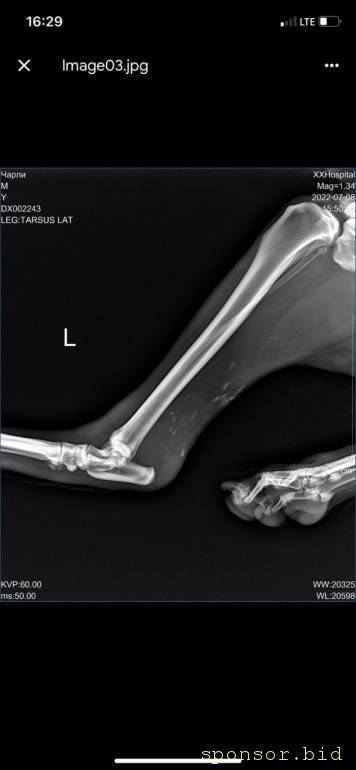

рентген

Помощь сбитой собачке - рентген 6.jpeg

Помощь сбитой собачке - рентген 1.jpeg

Помощь сбитой собачке - рентген 2.jpeg

Помощь сбитой собачке - рентген 3.jpeg

Помощь сбитой собачке - рентген 4.jpeg

Помощь сбитой собачке - рентген 5.jpeg

08.07.2022 г. передо мной на Варшавском шоссе сбили собаку, человек совершивший наезд даже не остановился и укатил дальше, я выбежала из машины, смогла остановить движение пары соседних полос, чтобы пес мог отползти на траву ( поднять и перенести не представлялось возможным, т.к. мне нельзя поднимать более 2 кг, более того непонятно что могла сделать собака в состоянии стресса и шока), после чего нашла парковку для машины и побежала к собаке, благо на тот момент несколько неравнодушных людей уже окружили его (это мальчик). Нами была вызвана полиция, составлено заявление ( но, думаем вряд ли кто-то будет этим заниматься.. так же сделан запрос в московскую службу видеофиксации, чтобы был сделан архив видео, если там есть камеры (тогда было не до этого, чтобы рассматривать есть ли они там), и в последствии приобщить к делу, или хотя бы найти того козла). Договорились со службой отлова, чтобы они на своей газели помогли довезти собаку до клиники шанс био, т.к. непонятно было что у нее с лапами, в клинике сделали рентген, несколько капельниц, обработали рану (т.к. задняя лапа разодрана до кости), взяли анализы, вкололи обезболивающие и отпустили.. т.к. у них нет стационара для бездомных, а так же хирурга, который мог бы сделать операцию. по заключению - кровоизлияние в глаз, открытая рана на левой заплюсне, вывих левого тбс (но вправить его нельзя, нужно делать операцию) порваны связки. по сумме в клинике оставили 14 500 руб. далее собаку отвезли в стационар надежда, с пятницы по воскресенье - обошлось в 10 552 руб (сам стационар, плюс лекарства, уколы и обработка ран, консервы, но он не ел). сегодня собаку возили на консультацию к хирургу в клинику беланта, было сделано дополнительно узи, на данный момент необходимо стабилизировать собаку, т.к. она еще в состоянии шока и с пятницы даже не ела, сейчас его опять повезли в стационар, необходимо еще делать уколы и обрабатывать рану, так же необходимо сделать 2 операции: на бедро (27200) и колено(55000), чтобы он смог передвигаться. в клинике заплатили 8167 с учетом лекарств. завтра планируется прием е еще одному хирургу в добрые руки, там по телефону озвучили цены на операции ниже чем в беланте, но нужен осмотр хирурга и его заключение. итого на данный момент на собачку ушло 33 219 руб. просим в сложившейся ситуации финансово помочь в судьбе пса, возможно найти ему любящих хозяев, на улицу его выкинуть уже просто невозможно, он там погибнет.. пес безумно умный, терпеливый, добрый, за все время ни разу не пытался агрессировать, укусить или что-то еще..